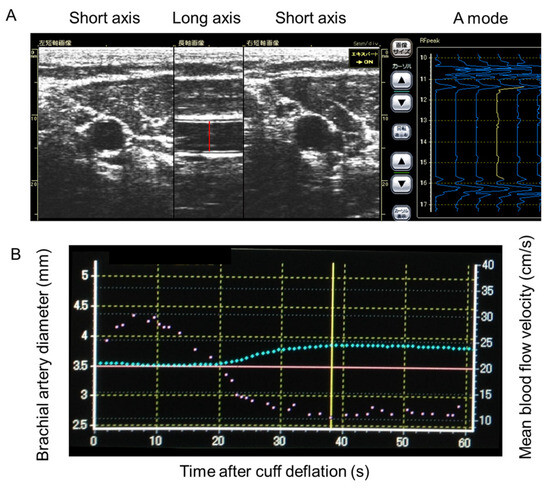

2.4. Assessment of Endothelial Vasomotor Function